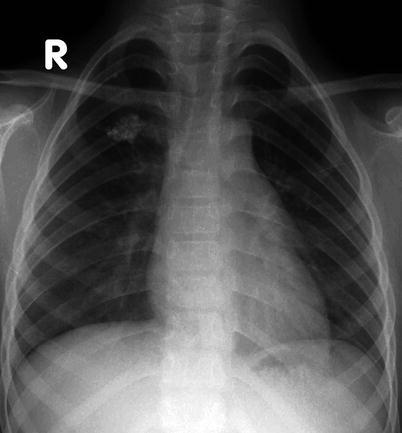

Lymphadenopathy (present in 92 %) with or without a visible Ghon focus is the radiographic hallmark of TB infection and usually involves the hilar and paratracheal regions. The Ghon focus may be too small to be radiographically visible but can also undergo caseation and calcify (Fig. 13.17). Disease progression may occur at the site of Ghon focus, within the regional lymph nodes, or following disease spread (Fig. 13.18). Parenchymal involvement in primary pulmonary TB most commonly appears as homogeneous consolidation, although it can appear patchy, linear, nodular, and mass-like. Caseation necrosis, liquefaction, or calcifications can be seen within the consolidation and can progress into extensive lung damage (Marais et al. 2004) (Fig. 13.19). Enlarged and edematous hilar, paratracheal, and subcarinal lymph nodes may cause compression of the adjacent bronchus and can lead to hyperinflation or atelectasis of the affected lung segment. Contrast-enhanced CT shows a characteristic appearance consisting of central areas of low attenuation with peripheral rim enhancement and obliteration of perinodal fat (Kim et al. 1997) (Fig. 13.20).

Fig. 13.17.

Primary TB infection. An asymptomatic 7-year-old boy had a chest x-ray as a school requirement, which reveals a calcified granuloma on the right upper lobe. This corresponds to a calcified Ghon focus, a sign of TB infection